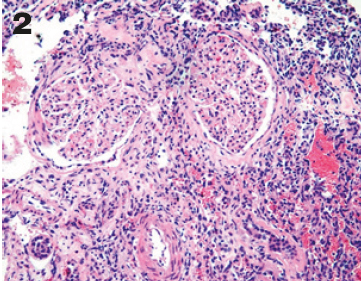

En la microscopía neoplasia con tendencia a formar papilas con focos de patrón sólido de células de núcleos con leve pleomorfismo, citoplasmas eosinofílico, escasas mitosis, además áreas que se disponen en patrón fusocelular y en canales vasculares. (Figura 2-6)

Figura 2-4. HE: Se puede observar el reemplazo del parénquima renal por la neoplasia vascular.

Fuente: Servicio de anatomía Patológica-Hospital de Especialidades Carlos Andrade Marín.